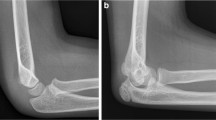

During the initial phase of set up of the structured reporting platform, various report templates had been created. While most templates focused on computed tomography or magnetic resonance imaging, some templates pertaining to conventional radiography were also developed. As basis for this proof of concept, we chose to focus on a rather simple use case using only plain radiographs. For the purpose of this study, we chose to use data from cases where plain radiographs of the ankle were obtained in the context of trauma (fracture/no fracture) and for which structured reports had been written using the above-mentioned platform (Fig. 1).

The “cx.ankle.trauma” template contained four drop-down menus where the reporting radiologist could select whether or not fracture, joint effusion, soft tissue swelling, or other relevant findings were either present or absent (Fig. 2). Apart from that, the template allowed for free-text entry of the corresponding finding. The source-code of the template can be found in Additional file 1.